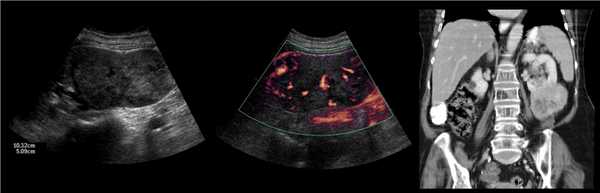

Рисунок. Двустороннее уретероцеле на УЗИ: в режиме ЦДК из верхушек уретероцеле определяется выброс мочи.

Рисунок. На УЗИ в уретероцеле определяется гиперэхогенная структура с акустической тенью — камень. Уретероцеле может являться одним из факторов, способствующих камнеообразованию.